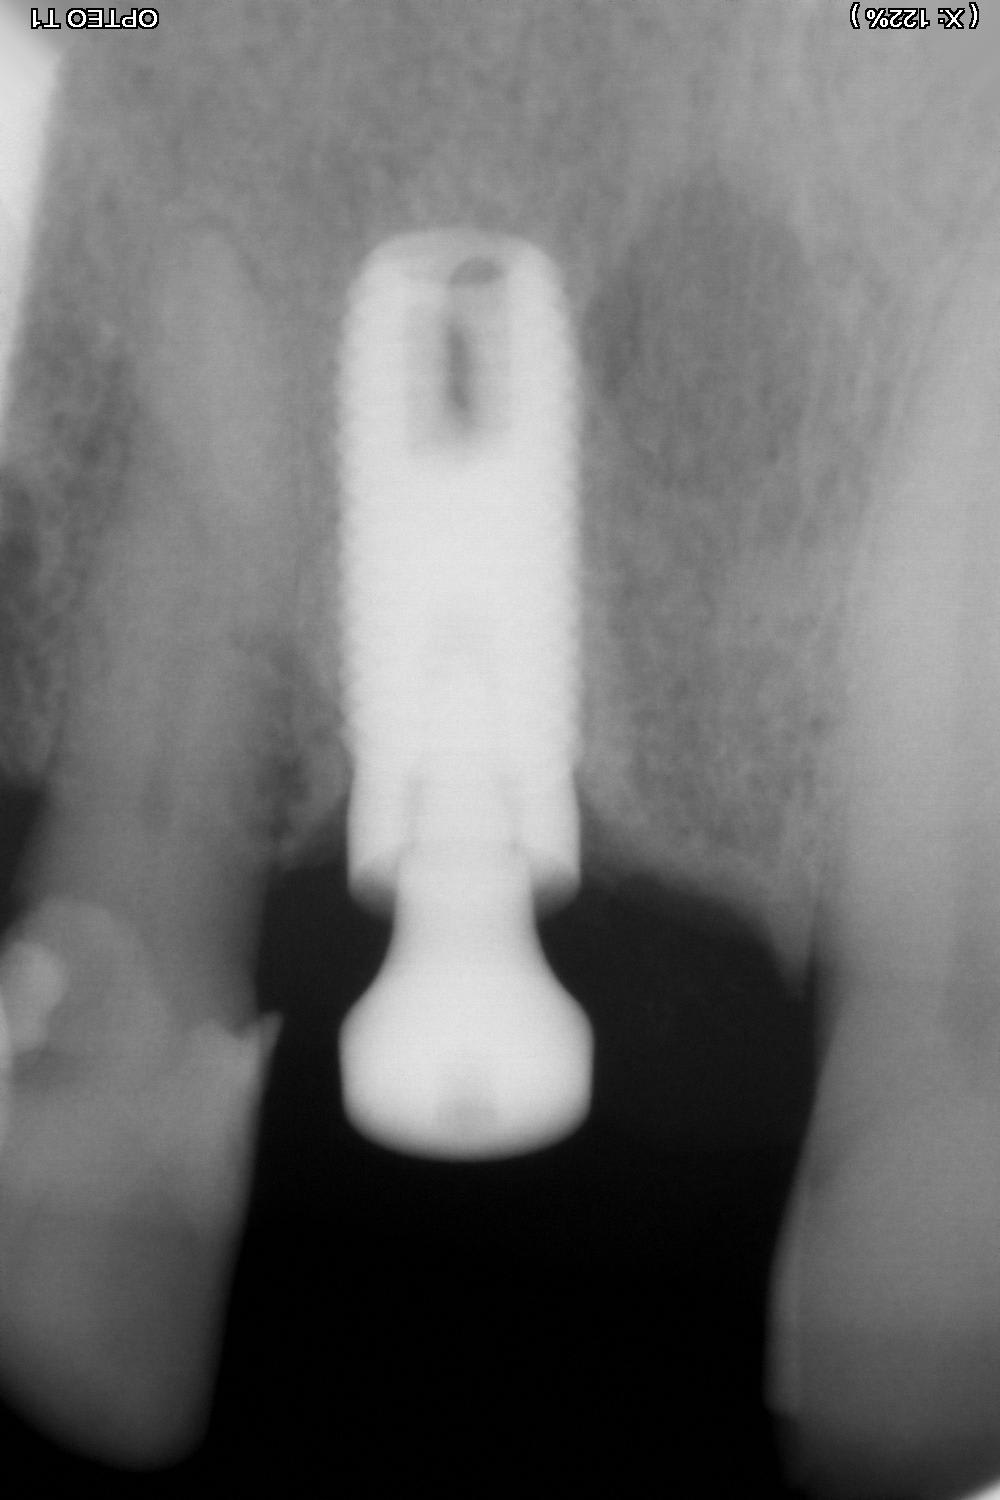

Quel est cet implant posé en 2004 à Strasbourg?

Je dirais Screw Vent de chez Zimmer ...

ouaip screwvent zimmer...

par contre la vis de cicat correspond absolument pas.....là je dirais que c'est un 4.7mm donc plateforme 4.5mm